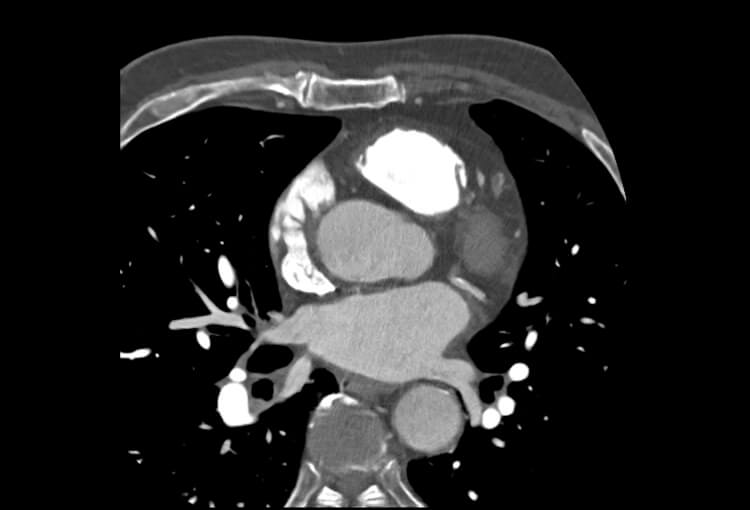

Before and After Denoising

120 kV / 20 mAs / 1 mm

Before FBP (Noise 189) VS After ClariCT.AI (Noise 46) 76% Denoising